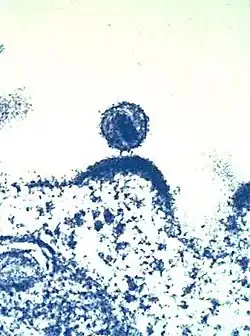

HI-Viren sammeln sich vor dem Verlassen der Immunzelle an der Membran.

HI-Virus, das sich aus einer Immunzelle herauslöst